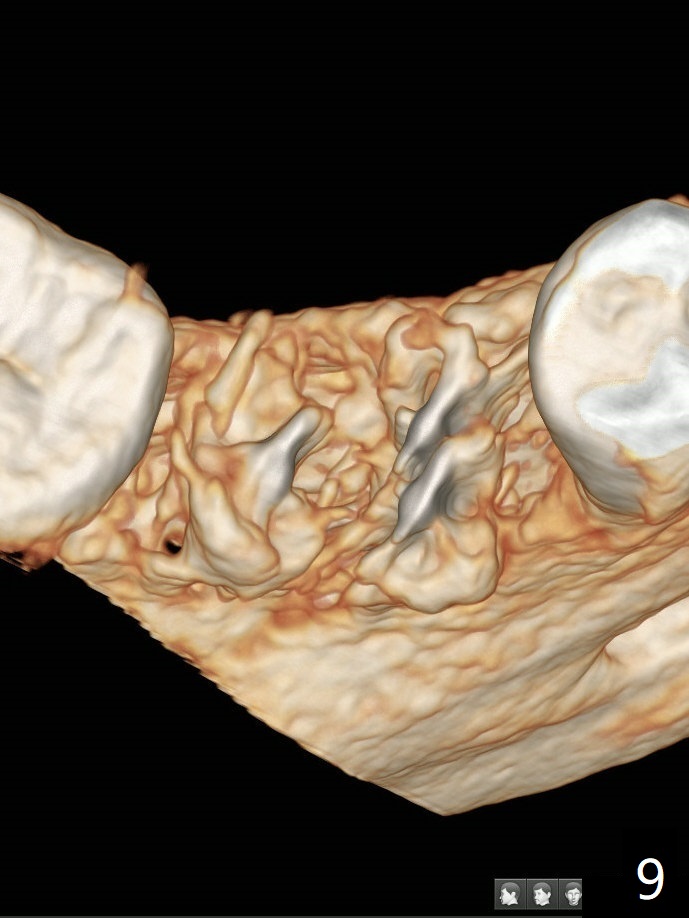

The tooth #30 of a 47-year-old woman has lower buccal crest (Fig.1-3 ^). To prevent post-extraction buccal plate collapse, closed socket shield (Fig.6,8-10 *) will be conducted in the mesial (Fig.1,4-6) and distal (Fig.2,7-10) roots. To decrease vibration, the buccal edge of the roots will be trimmed first (Fig.5,6 a) before root section (Fig.6 b).